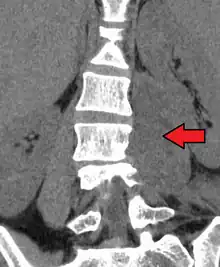

Paraspinal abscess in the psoas muscle | |

Psoas abscess is a collection of pus in the iliopsoas muscle compartment.[1][2] It can be classified into primary psoas abscess (caused by hematogenous or lymphatic spread of a pathogen) and secondary psoas abscess (resulting from contiguous spread from an adjacent infectious focus).[2]

Psoas abscess may be caused by lumbar tuberculosis. Owing to the proximal attachments of the iliopsoas, such an abscess may drain inferiorly into the upper medial thigh and present as a swelling in the region. The sheath of the muscle arises from the lumbar vertebrae and the intervertebral discs between the vertebrae. The disc is more susceptible to infection, from tuberculosis and Salmonella discitis. The infection can spread into the psoas muscle sheath.[3]